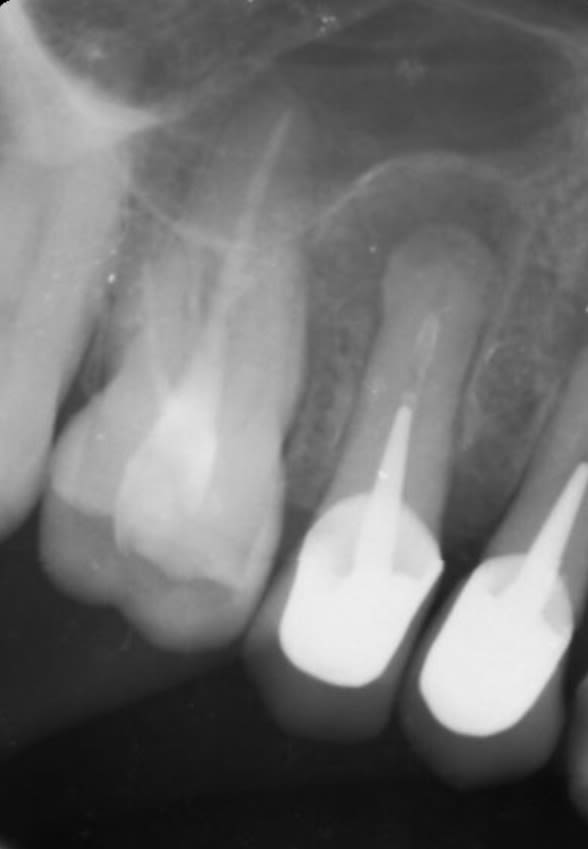

Regardez ce que j’ai fait ... Petit échec personnel.

Je vois une lésion avec un traitement approximatif avec un bout de racine bizarroïde. « Pas de problème madame, vous allez voir on va retraiter tout ça » et j’ai même ajouté « vous allez voir qui c’est le patron » :)) . Je retraite mais impossible d’aller jusqu’au bout. Je me suis dit « je vais lui balancer la purée et la chauffer à mort pour atteindre l’apex »

Une fois le traitement fini je me dis « tiens y a comme une petite giclée avant d’atteindre l’apex ». Et ça n’est qu’en rentrant chez moi que je me suis dit que c’était un cémentome avec plus loin une lésion kystique . Un an après bien entendu lésion toujours présente. Davier à sortir , une belle perte de temps. Je vous ai fait un petit zoom pour qu’on différencie bien l’apex du cémentome (ou peut-être ostéocondensation )

je ne comprends pas pourquoi extraction, il y a des signes cliniques? La lésion n'a pas augmenté de volume, je dirais même pour ce qu'on en voit qu'elle a réduit. En quoi cette dent est gênante, des études ont montré que certains lésions mettaient des années à réduire et même certaines jamais d'un point de vue radiographique. Véritablement je ne comprends pas.